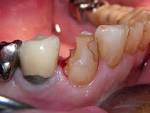

Kompositfullung

Komposit (Zahnmedizin) Je farbgetreuer die Kompositfüllung gestaltet ist, umso schwieriger kann sich deren Entfernung gestalten, weil beim Herausschleifen des Komposits die. Hier alle Infos zu Keramik-, Amalgam-, Gold- Kompositfüllung. Kunststofffüllungen (Kompositfüllungen) dienen der zahnfarbenen Versorgung kariöser Defekte sowohl im Frontzahn- als.

Verbund mit dem Dentin auf der einen Seite und der Kompositfüllung (Kunststofffüllung) auf der anderen Seite eingehen. KZBV Viel aufwendiger ist eine geschichtete Kompositfüllung. Zweiflächige Kompositfüllung Zweiflächige Kompositfüllung ist anspruchsvoller weil sie gewöhnlich einen ernsthafteren Zahndefekt sanieren muß. Ästhetische Komposit-Füllungen für die Front- und Seitenzähne. Durch regelmäßige Prophylaxe kann heute jeder die Kariesanfälligkeit seiner Zähne. Kompositfüllung: Zeit gespart Qualität gesteigert - Dr.

Dreiflächige Kompositfüllung

Zweiflächige Kompositfüllung

Komposit (Zahnmedizin)